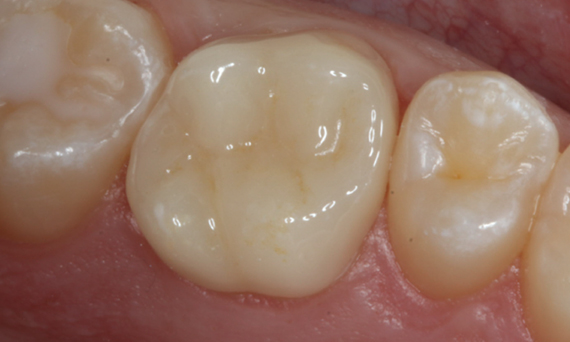

Before: Fractured ceramic restoration made from a leucite-reinforced glass-ceramic after a clinical service time of 12 years.

After: Chairside-fabricated restoration made from an advanced lithium-disilicate ceramic CEREC Tessera.